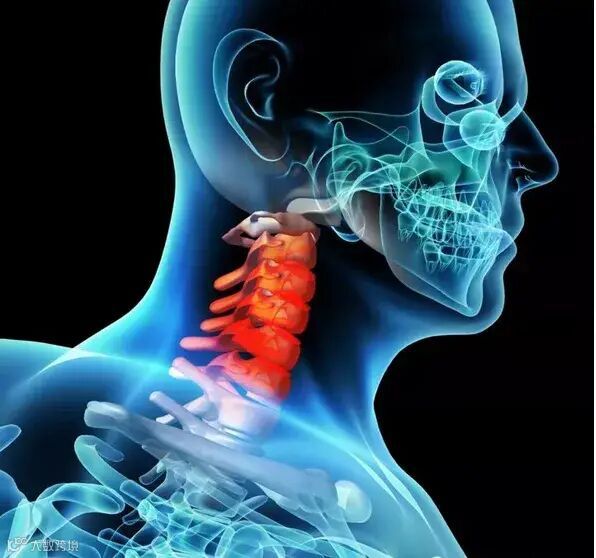

一.什么是颈椎病?

图中红色的部分就是人体的颈椎,它是由7块椎骨从上而下排列组成的。在这7块椎骨之间,有从上往下走的脊髓,脊髓就像我们的黄河一样,从颈椎一直流淌经过胸椎,再到腰椎,再到骶椎。其中颈椎处于这条河的上游,如果颈部的脊髓出状况,下游的全部脊髓神经都可能受影响。所以颈部脊髓的严重损害常导致截瘫,所谓截瘫,就是从某一个水平面以下的所有肢体感觉和运动功能均丧失。相当于上游被截流,下游就没水了。脊髓如下图黄色部分。